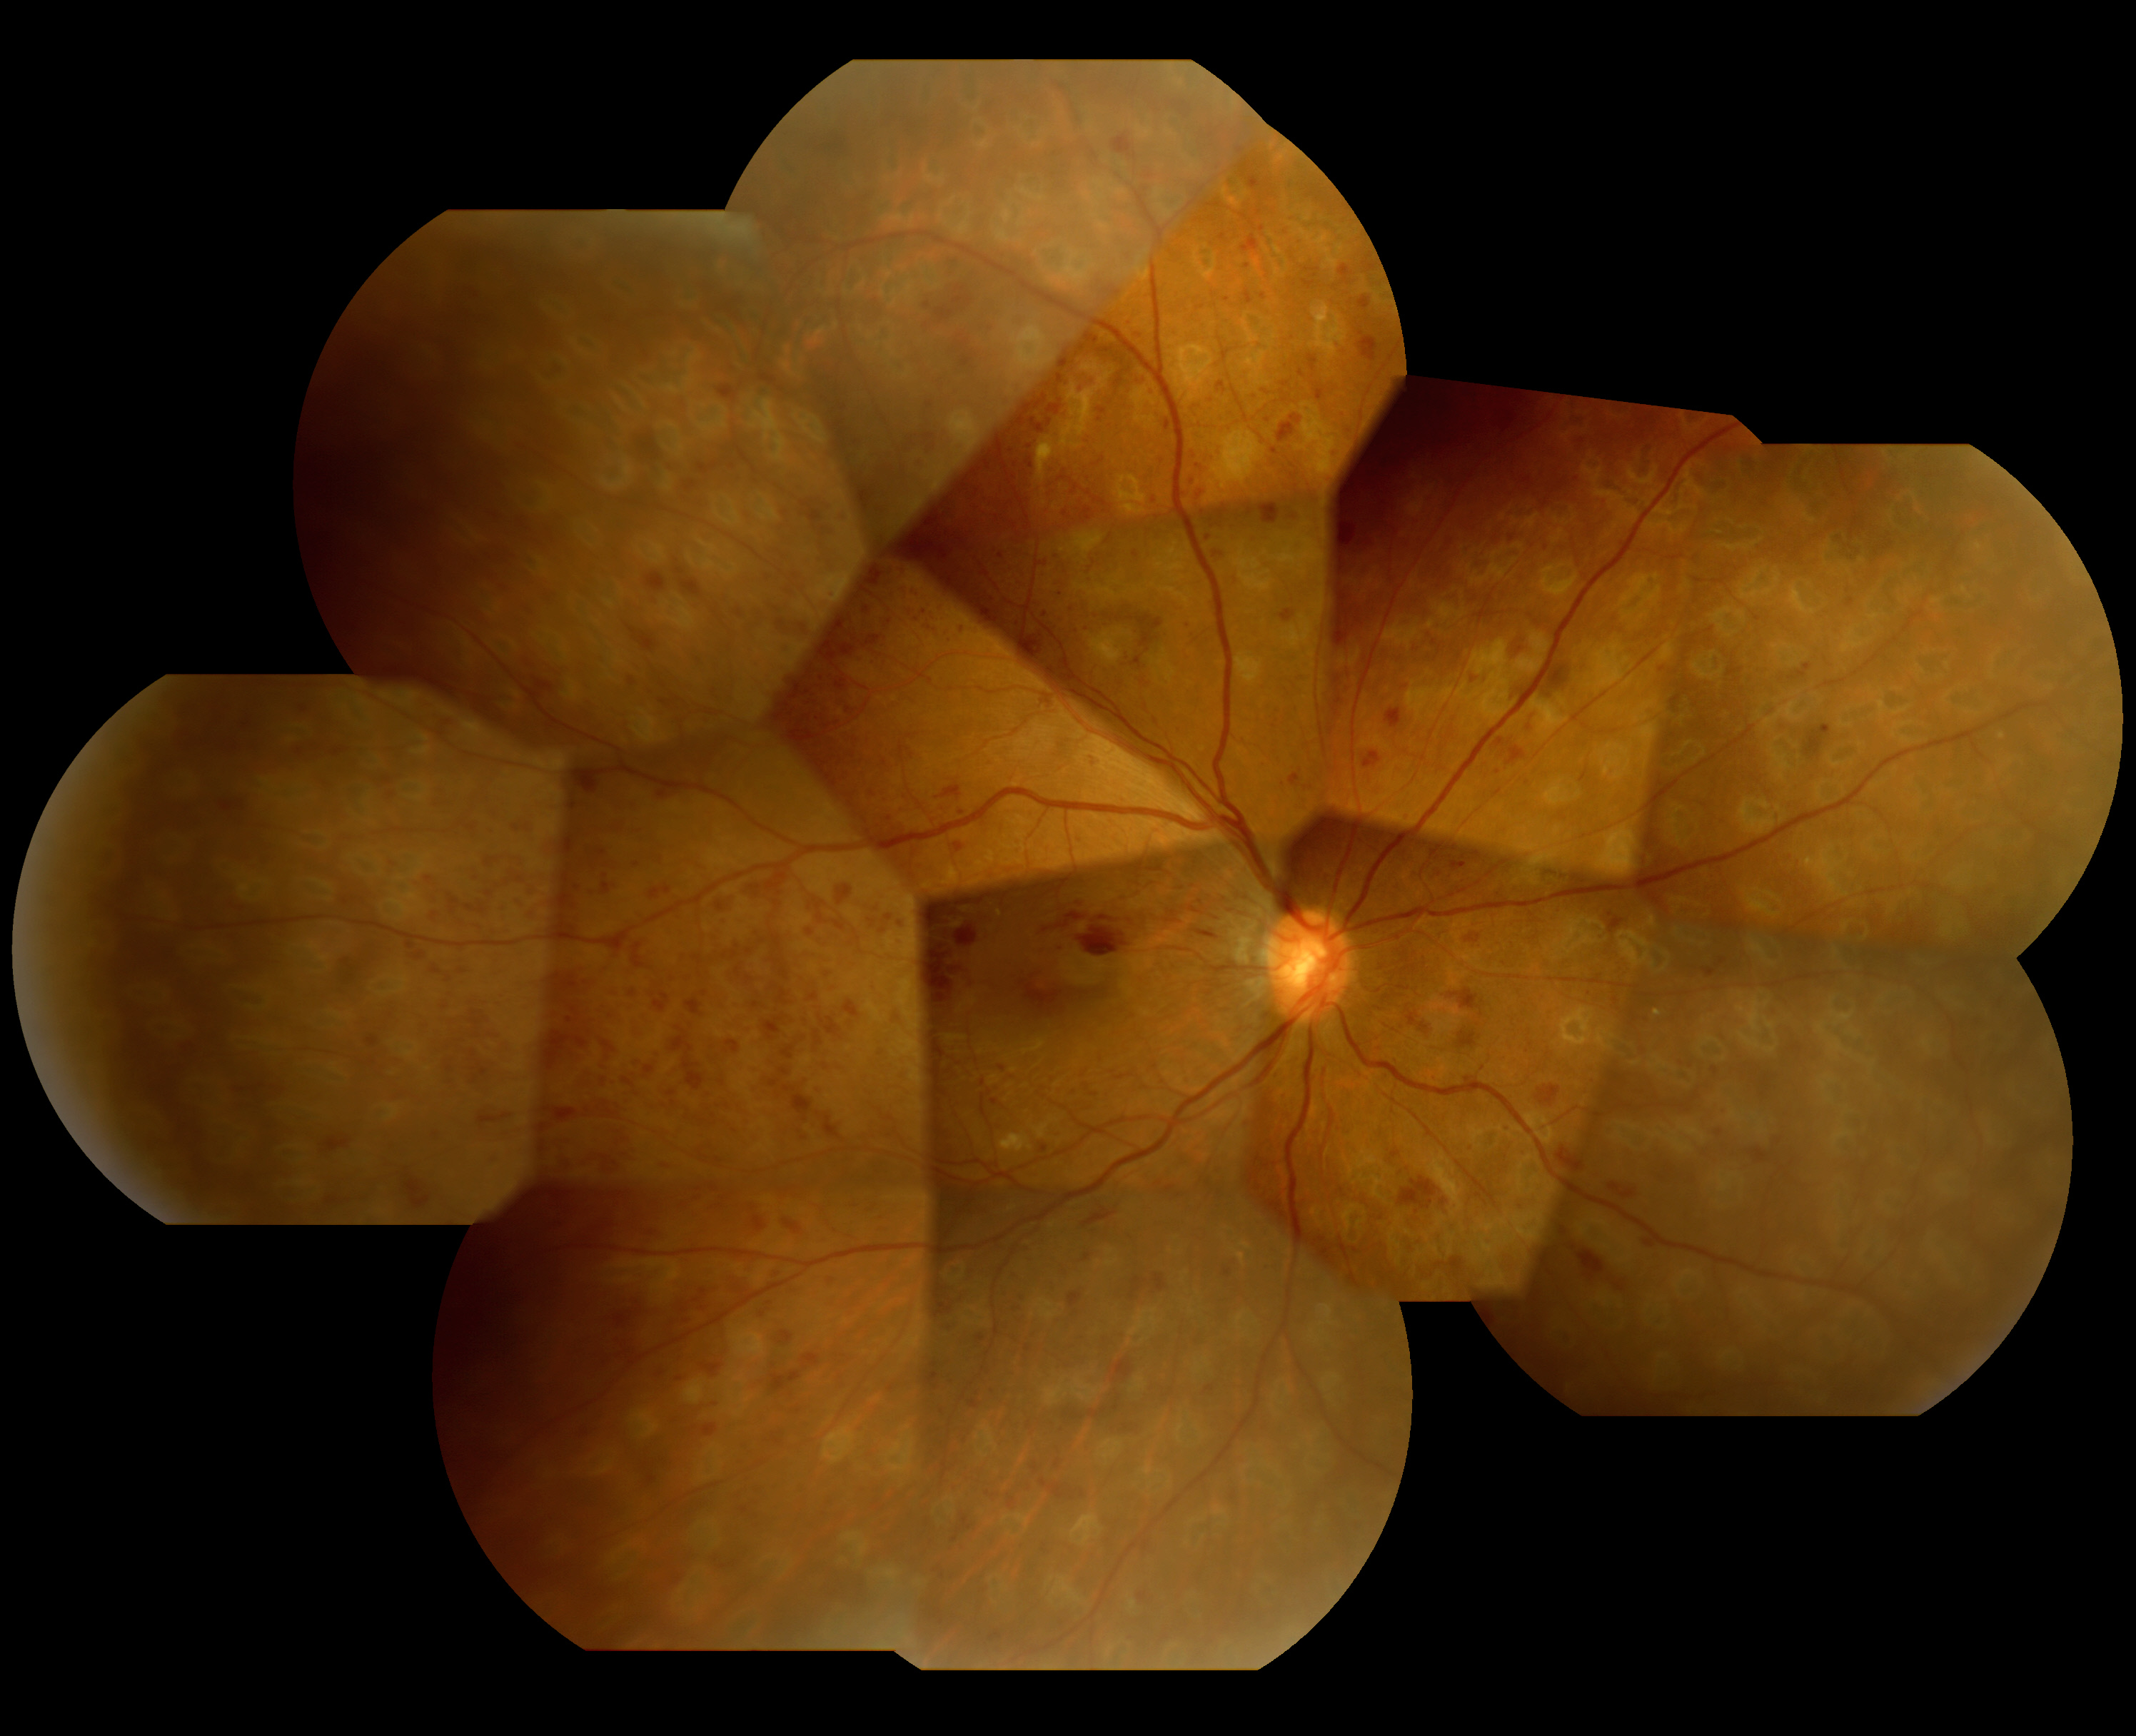

2.前増殖糖尿病網膜症

| 中期の網膜症 | 毛細血管がつまり血管閉塞を生じます。血管閉塞した網膜は虚血におちいり、軟性白斑という所見が生じます。 | 虚血網膜は放置することによって、新生血管が生じ、硝子体出血や増殖膜のもとになるため、この段階で、的確なレーザー治療(網膜光凝固術)をしっかりと行っておくことが非常に重要になります。 |

軟性白斑 |

レーザー光凝固施行前の糖尿病網膜症  レーザー光凝固施行後の糖尿病網膜症 |